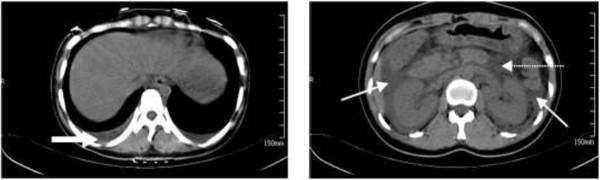

A total of 218 patients were diagnosed with hemorrhagic fever with renal syndrome during the 6-year study period. Only 2.8% (6/218) of the total hemorrhagic fever with renal syndrome patients were diagnosed with acute pancreatitis. The first symptom for all six of the patients with acute pancreatitis was fever. All six patients experienced hemorrhage and thrombocytopenia during the disease course, which was different from general acute pancreatitis. In addition, we presented two misdiagnosed clinical cases.

本研究共纳入 218 例肾综合征出血热患者,其中仅 6 例(2.8%)被诊断为急性胰腺炎。6 例急性胰腺炎患者的首发症状均为发热。与一般急性胰腺炎不同的是,这 6 例患者在病程中均出现出血和血小板减少。此外,我们还介绍了两例误诊的临床病例。